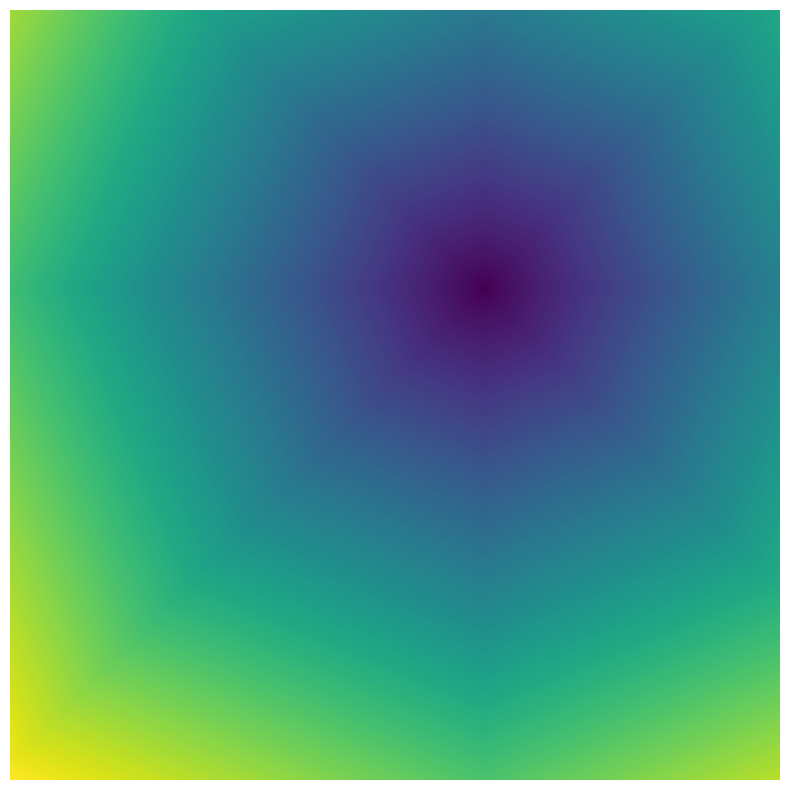

Generally, given an exact, full annotation of an object, such a Euclidean signed distance map encodes also information on the shape of an object. But when using a weak ground truth , where and , inferring a correct extent and shape of the objects is nontrivial. As shown in 1(b), Euclidean distance calculated from a point label source grows radially, regardless of the actual shape of the object, and thus makes little sense from an information point of view. Under the assumption of intra-object homogeneity and inter-object contrast (w.r.t intensities), this problem can be circumvented to a degree by using a distance function that takes also intensity values into account. An example of a commonly used distance measure with an intensity component is the Geodesic distance ([34]). Let denote a path between , with and being neighbors under a chosen adjacency relation. Reusing the notation from before, a Geodesic distance map from the boundary of the ground truth class , , can be defined as

While setting the parameter to actually results in a taxicab distance, which can be seen as a discrete approximation of a Euclidean distance, setting focuses purely on image intensities. We call the latter simply Intensity distance, . From here on we shall use the term Geodesic distance, , to denote the setting of , and Euclidean, , to denote the setting .

Entirely on the other side of the spectrum from the Euclidean are the fully intensity based distances, such as the Minimum barrier distance (MBD) from [31]. It is not only calculated exclusively on the image intensity space, but also effectively independent of the path length in space. Given the definition of above, the MBD map from the boundary of ground truth class , , can be defined as:

| (4) |

MBD is actually only a pseudo-distance, as the reflexivity property may be violated (i.e. it may be that even when ). As opposed to full supervision, this can be a very desirable property in the case of weak labels.

Both the Intensity and the Minimum barrier distance are defined exclusively on the image intensity space. However, from the examples of distance map in 1(d), we can notice that the values still increase somewhat radially from the annotation. This behaviour is similar to the one of the Geodesic distance in 1(c) (which actually includes the spatial proximity in its definition), and is due to the summing operator in the general Geodesic distance definition in Equation 3. While the intensities of two neighboring pixels on a path may be the same, that will rarely be the case in real life, noise riddled images. This makes the Intensity distance function approximately monotonically increasing with increasing length of the path (in space), even on paths where the intensity is mildly fluctuating (e.g. consider a path with even pixels intensity value of and odd pixels intensity value of ). One could thus argue that such a definition of a distance, despite being based exclusively on intensities, is still capable of loosely encoding the spatial distance information.

On the other hand, while we can see that the MBD based maps are similar to Geodesic and Intensity ones (1(e)) with respect to the object shape recovery, they have a less pronounced and smooth increase in the values outward from the source point.

In contrast to Euclidean distance, the Geodesic, Intensity and Minimum barrier distance maps all encode contrast sensitivity and preserve the object structures by harnessing the intensity information of the underlying image. This holds even when calculated from point sources. In practice, using such maps for network training could mean a lower penalty for false positives that occur farther from the point annotation but are close to it in intensity. Thus still enabling the propagation of a sort of shape information (as it can be inferred from the raw image intensities).